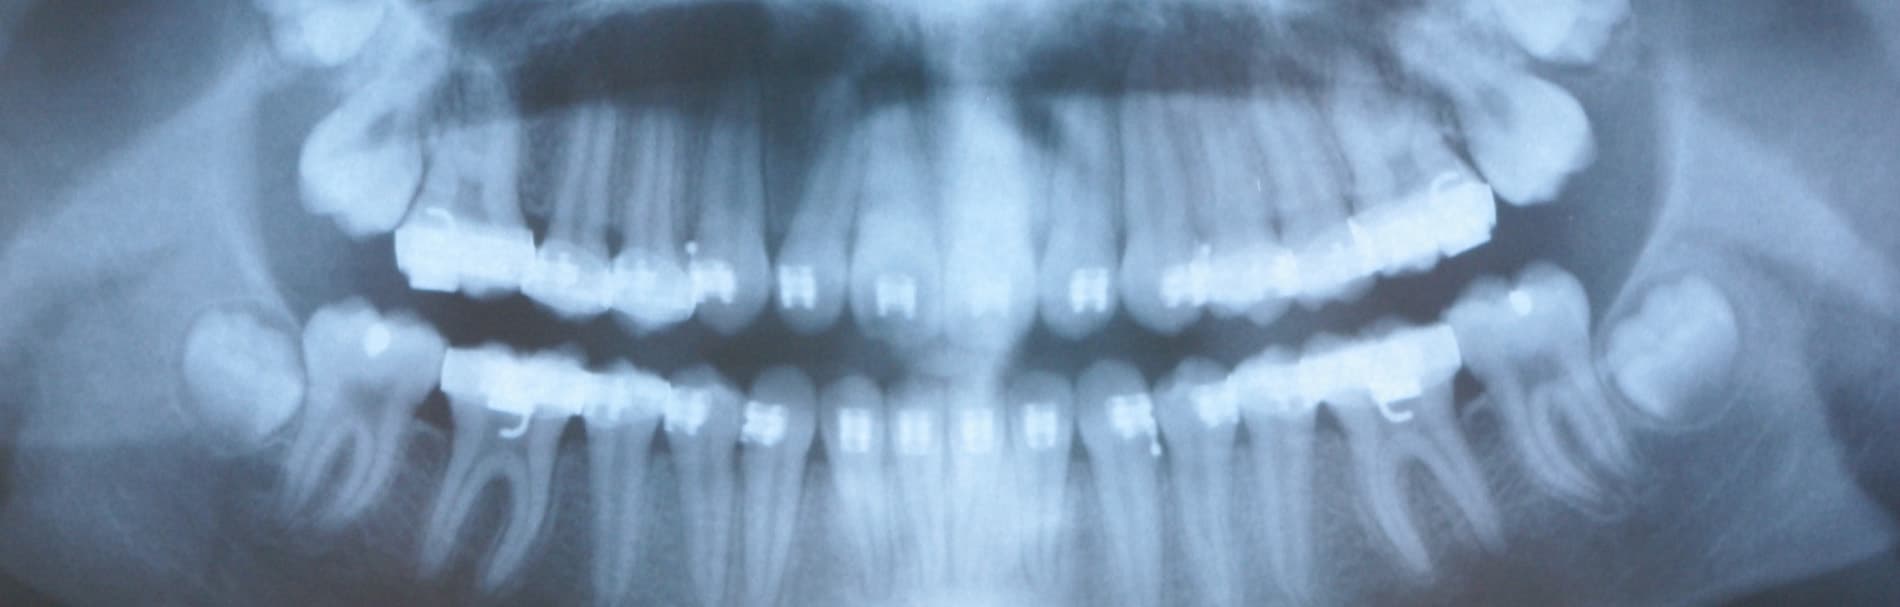

Met behulp van een grote overzichtsröntgenfoto beoordeelt de tandarts het aantal en de ligging van de tanden en kiezen en de grootte en vorm van de wortels en de kaken. De officiële naam van deze foto is orthopantomogram, afgekort OPG. Deze foto is onder meer van belang om te bepalen, wanneer het beste met een (ortho)behandeling kan worden gestart. Op dergelijke foto’s is nog veel meer te zien. Zo kan men o.a. nagaan of alle tanden en kiezen zijn aangelegd. Vaak wordt ook een OPG gemaakt om te kijken, of er voldoende kaakbot aanwezig is om implantaten te plaatsen.